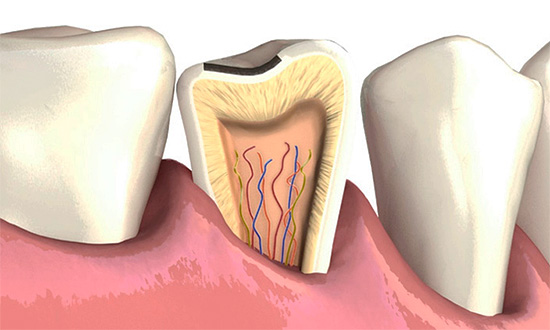

Tuttavia, la carie è piuttosto insidiosa e in alcuni casi può svilupparsi in modo asintomatico fino a fasi in cui sarà richiesta la rimozione di una parte significativa della dentina e talvolta la depulpazione (rimozione del nervo). Ecco perché la definizione di patologia nelle cliniche dentali viene spesso effettuata utilizzando attrezzature moderne e le lesioni profonde nascoste nei denti vengono rilevate utilizzando metodi ad alta tecnologia.

Questo metodo di diagnosi della carie dentaria è particolarmente efficace nelle situazioni in cui è necessario identificare la carie profonda che non presenta manifestazioni esterne evidenti. Ad esempio, se il punto di violazione dell'integrità dello smalto è nascosto dalla parete di un altro dente o gomma. Sulla radiografia, tutte le cavità danneggiate interne sono ben riconosciute, ma nella maggior parte dei casi non consentono di riconoscere la carie nelle prime fasi di sviluppo.

- Sulla base di una radiografia, è possibile distinguere la carie profonda lesioni non cariose dello smalto e complicanze della carie (pulpite e parodontite).